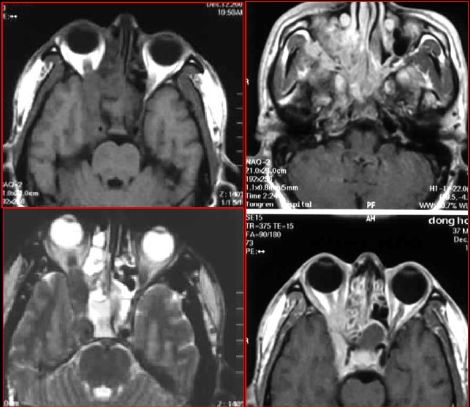

蝶窦炎—眶尖综合症

鼻窦炎—眶尖综合症